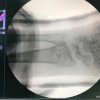

Cirugias en El Salvador - Cirugías de Muñecas y Manos

Los procedimientos más comunes en cirugía de la mano son aquellos destinados a reparar traumatismos, incluyendo lesiones de tendones, nervios, vasos sanguíneos, y articulaciones; huesos fracturados; y quemaduras, cortes, y otros daños de la piel.